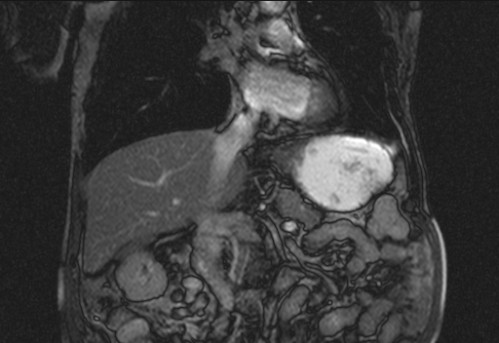

Auffälliges Abdomen bei der Vorsorgeuntersuchung einer älteren Dame

ICD: C64

68 Jahre alte Frau. Sie geht zur Darmspiegelung im Rahmen ihrer Krebsvorsorgeuntersuchung. Der Internist bemerkt bei der ergänzenden sonografischen Untersuchung des Abdomens einen auffälligen Befund.